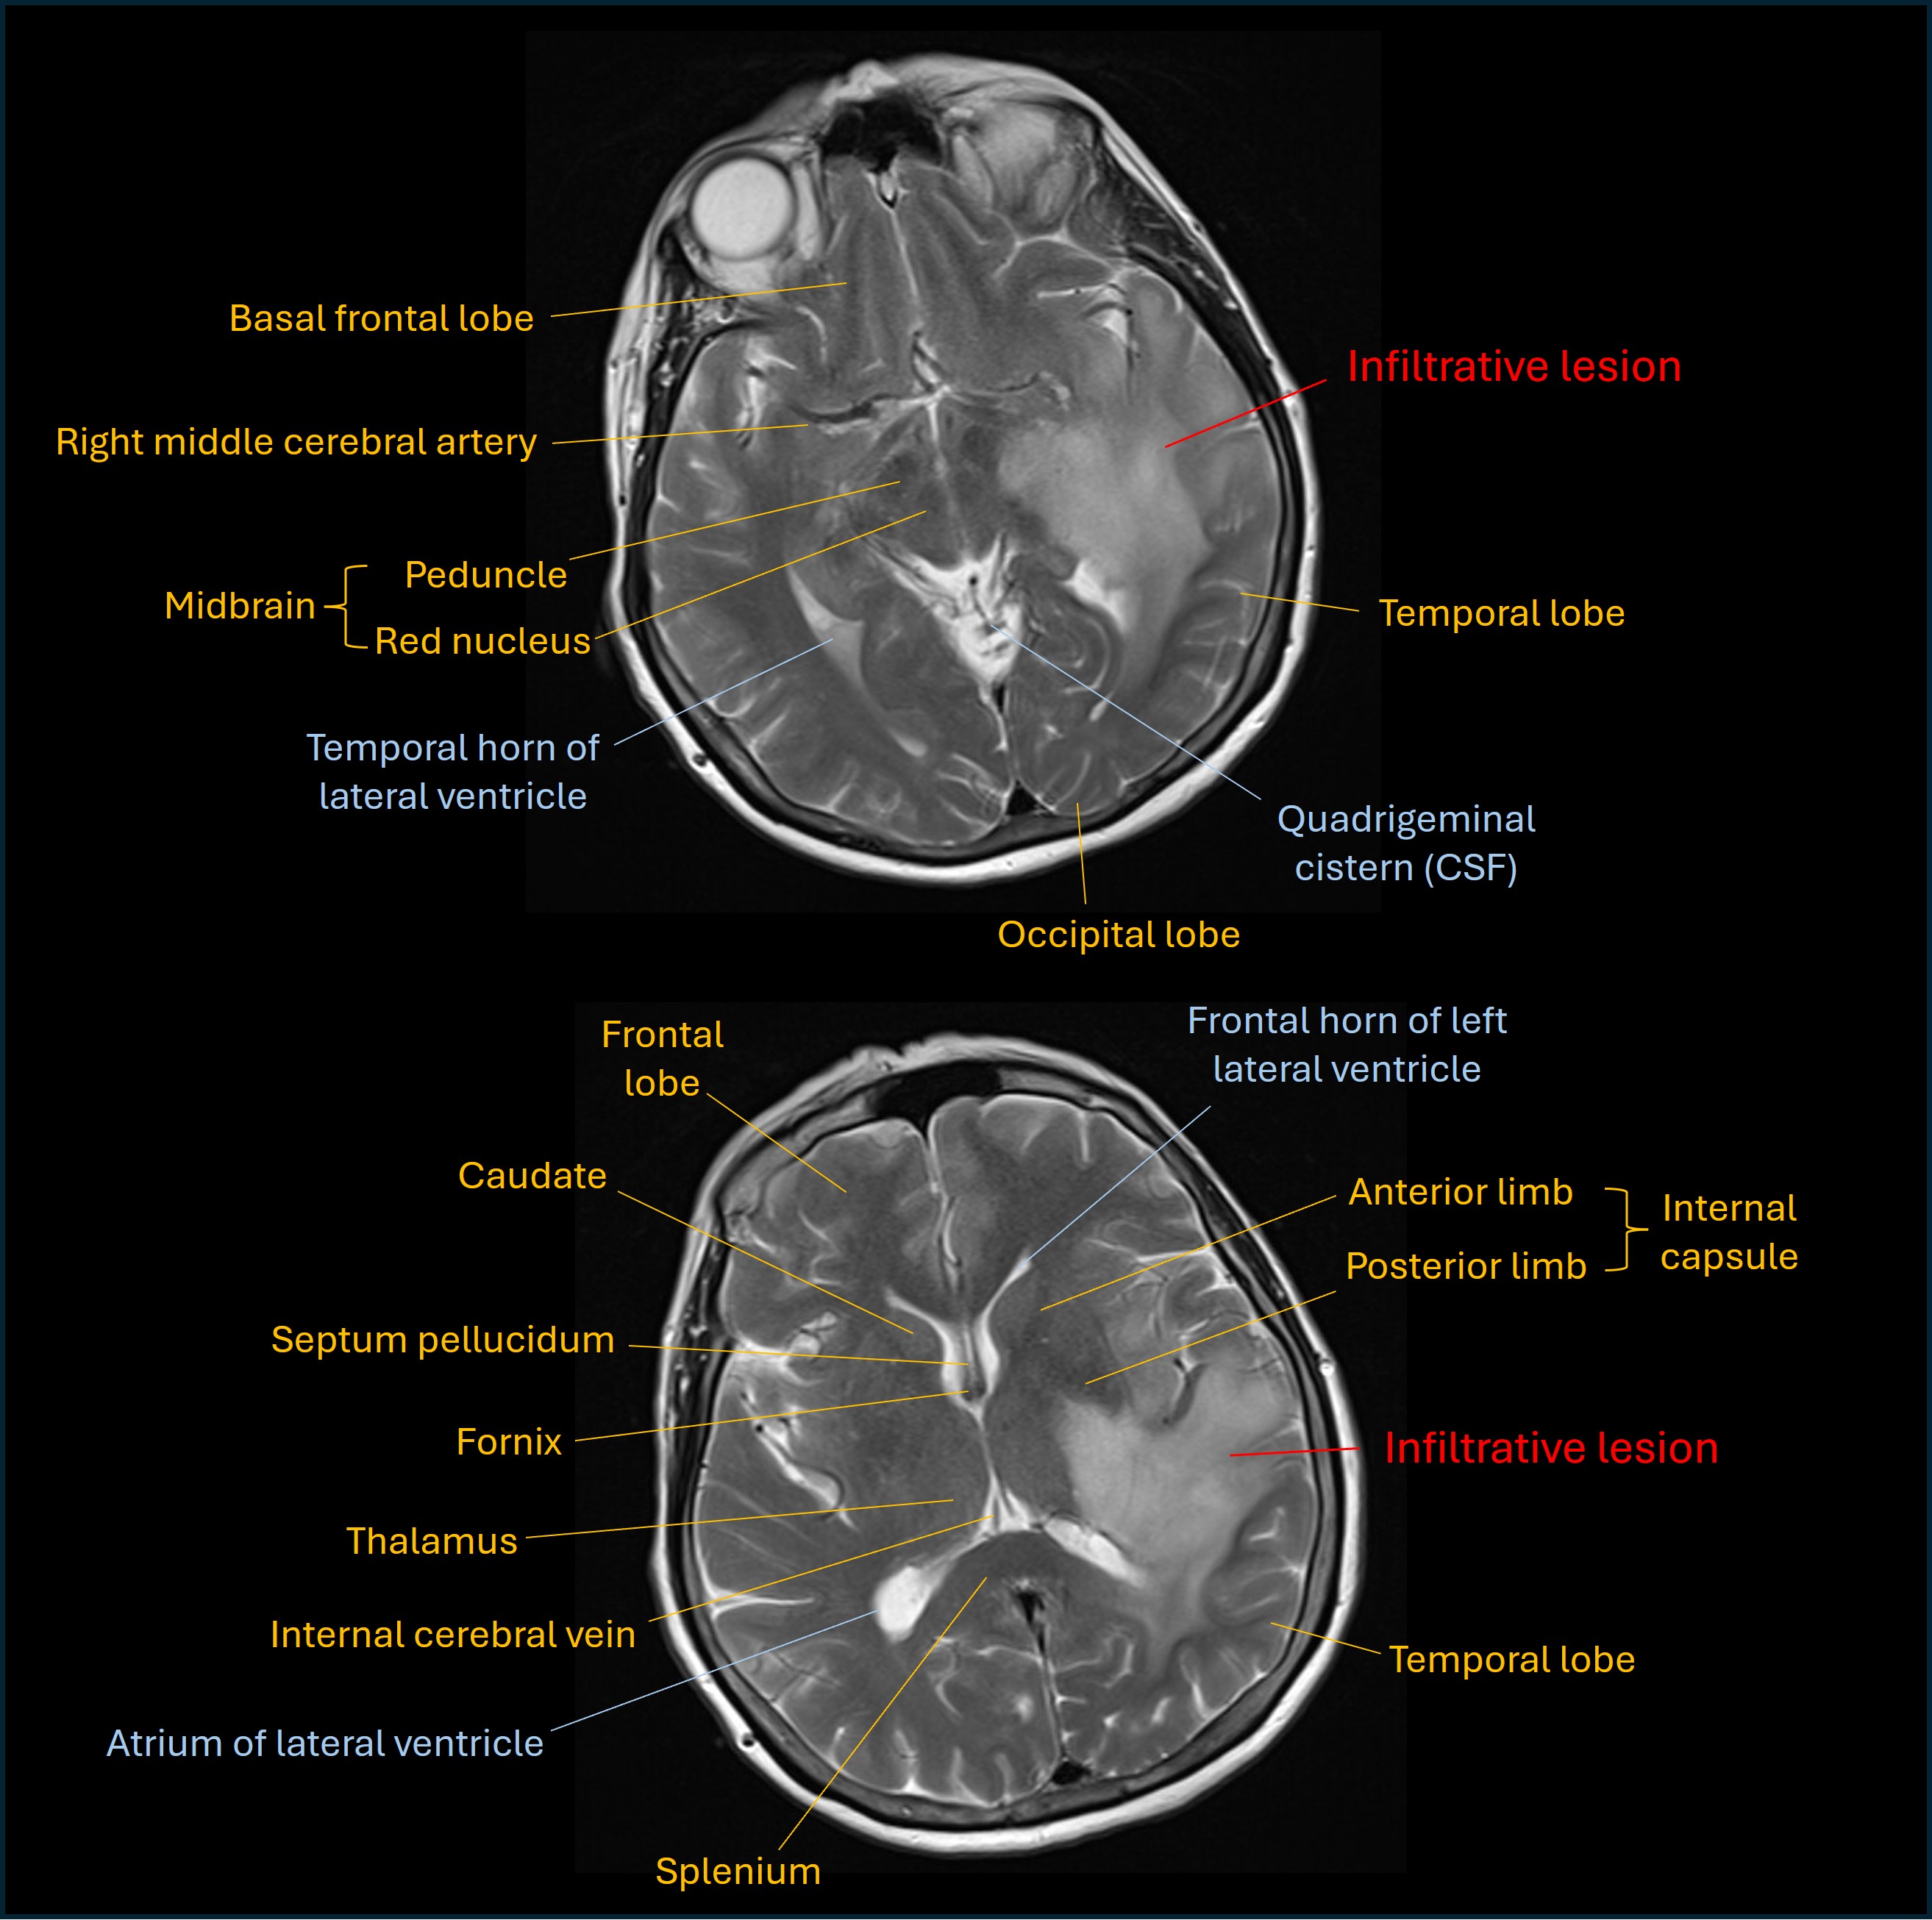

An MRI showed an extensive left temporoparietal lesion with a degree of mass effect on adjacent cortex and with surrounding oedema. The lesion extended inferiorly to the thalamus and upper midbrain. T2 images are shown below.

T2 MRI

The appearances suggested a low-grade lesion (likely glioma) with no contrast enhancement visible.

However, the rapid onset and progression raised concern for a higher-grade lesion - it was felt possible this could be a low grade lesion undergroing transformation to a higher-grade type.